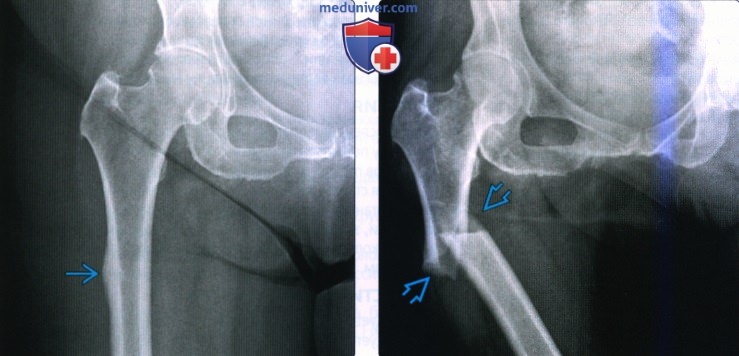

Классификация переломов диафиза бедренной кости: Иллюстрации и информация